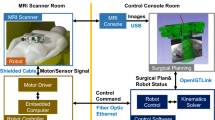

This paper presents new quantitative data on a signal-to-noise ratio (SNR) study, distortion study, and targeting accuracy phantom study for our patient-mounted robot (called Arthrobot). Arthrobot was developed as an MRI-guided needle placement device for diagnostic and interventional procedures such as arthrography.

We present the robot design and inverse kinematics. Quantitative assessment results for SNR and distortion study are also reported. A respiratory motion study was conducted to evaluate the shoulder mounting method. A phantom study was conducted to investigate end-to-end targeting accuracy. Combined error considering targeting accuracy, respiratory motion, and structure deformation is also reported.